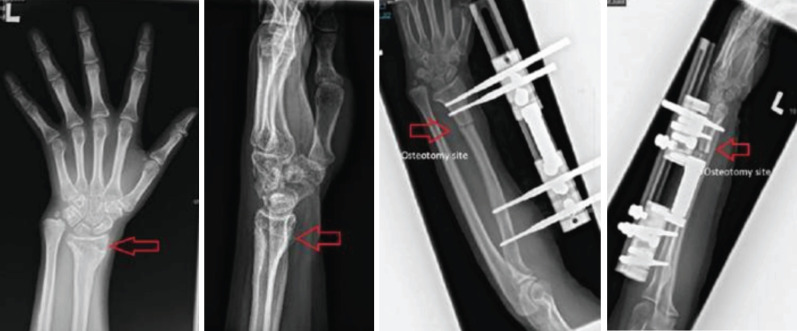

桡骨远端骨折是儿童前臂骨折中最常见的类型。肢体损伤最严重的后果是生长停滞,这可能导致畸形甚至肢体长度的显著差异。因此,我们想和大家分享我们治疗一位在事故中身体受伤后左桡骨停止生长的病人的经验。案例介绍:我们遇到了一个10岁的女孩,她卷入了一场道路交通事故。患者左侧桡骨远端持续闭合性骨折(Salter Harris 2)。患者晚期求医,采取破骨术、切开复位、左桡骨k线固定骨折,但骨愈合后左侧桡骨生长停止。据观察,她的左桡骨比右桡骨短约4厘米。她做了左桡骨截骨手术并植入了LRS。术后6个月后,她的左上肢没有明显缩短,桡骨长了大约4厘米。左桡骨延长后无神经血管损伤。手术一年后,病人说她的左上肢没有任何不适。尽管ilizarov方法很流行,单轨外固定架,也被称为LRS,是桡骨延长的一种选择。在我们的情况下使用了LRS,结果证明了它的有用性。

Fractures of the distal radius are the most common type of forearm fractures seen in children. The most serious outcome of physeal injuries is growth arrest, which can result in deformity and even significant differences in limb length. Therefore, we'd like to share our experience with treating a patient whose left radius stopped growing after she had a physeal injury in an accident. Case presentation: we encountered a 10-year-old girl, who was involved in a road traffic accident. She sustained closed fracture distal end left radius (Salter Harris 2). She sought medical assistance late, so osteoclasis, open reduction, and a k-wire on her left radius to fix the fracture, however it was complicated with growth arrest of left radius after the bone united. It was observed that her left radius was around 4cm shorter than her right. She had an osteotomy performed on her left radius and a LRS implanted. After six months post-surgery, there was no visible shortening of her left upper limb, and the radius had grown by around 4cm. There was no neurovascular impairment after left radius lengthening. After a year had passed after her operation, the patient said she had no complaints about her left upper limb. Despite the prevalence of the ilizarov method, the monorail external fixator, also known as LRS, is an option for bone lengthening of the radius. The LRS was utilised in our situation, and the results demonstrated its usefulness.